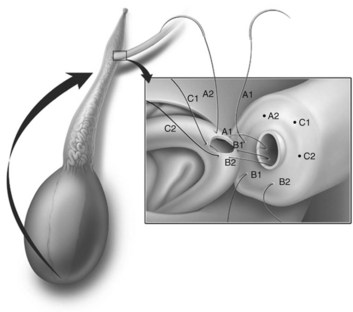

This method, originally described as the triangulation technique, was introduced by Berger (1998). There are several advantages of the methods over previous techniques (see Table 22–3) (Goldstein, 1999). The setup is identical to that for the classical end-to-side vasoepididymostomy. After the vas is fixed to the opening in the epididymal tunica, six microdots are placed on the cut surface of the vas in an identical fashion to that described for vasovasostomy. The epididymal tubule selected is dissected with blunt microscissors and the micro needle holder until it is free of surrounding tissue and prominent. The tubule is then stained with indigo carmine. Using 10-0 monofilament nylon sutures approximately 2 inches in length, double armed with 70-µm diameter fish hook–shaped tapered needles, three sutures are placed in the epididymal tubule in a triangulation fashion. The apex of the triangle faces the inferior edge of the vasal mucosa. The needles are not pulled through but left in situ, creating a triangle of needles (Fig. 22–35). Using a 15-degree microknife with the blade pointing upward, a generous opening is made in the epididymal tubule in the center of the triangle created by the three needles (Fig. 22–36).

Figure 22–36 Using a 15-degree microknife with the blade pointing upward, a generous opening is made in the epididymal tubule in the center of the triangle created by the three needles.

The three needles are then pulled through. The six needles are now laid out so as to avoid a spaghetti-like tangle. A glass slide is touched to the fluid exuding from the opening in the epididymal tubule and mixed with human tubal fluid media, covered with a coverslip, and examined by the surgeon using the separate bench microscope under 400-power magnification. If sperm are present (whether motile or not), the decision is made to proceed with the anastomosis. Sperm are aspirated into micropipets first (Fig. 22–37) and expressed into human tubal fluid media and sent for cryopreservation if motility is observed. Sperm that initially appear immotile, when mixed with human tubule fluid, often regain motility adequate for successful cryopreservation. Even immotile sperm should be placed in the media and evaluated for potential cryopreservation. If the needles are pulled through before placing the microsurgical sutures or before making an opening in the epididymal tubule, epididymal fluid and sperm would immediately leak through the suture hole, causing the tubule to collapse. This makes placement of subsequent sutures and creation of the opening in the tubule considerably more difficult. Leaving the needles in the epididymal tubule before making the opening also prevents accidental cutting of the sutures when making the opening in the center of the triangle. After abundant sperm have been aspirated into micropipets and cryopreserved, the six needles are passed inside out the vas deferens exiting through the six previously placed microdots in the order indicated (Fig. 22–38). Each pair of sutures is then sequentially tied beginning with suture a1 and a2, then b1 and b2, and finally c1 and c2. Tying of these sutures intussuscepts the epididymal tubule into the vas lumen (Fig. 22–39). This creates a water-tight closure (Fig. 22–40). In addition, the flow of epididymal fluid from the epididymal tubule into the vas deferens tends to plaster the edges of the epididymal tubule against the mucosal walls of the vas deferens, further helping create a leakproof closure. The second layer of the anastomosis is completed in an identical fashion to that described for the classical end-to-side operation described earlier (Fig. 22–41A and B).

For anastomoses to small epididymal tubules such as those found in the caput or to the efferent ductules (Chan et al, 2005), the three-stitch triangulation technique may be impossible. We now employ a two-stitch longitudinal intussusception technique for all vasoepididymostomies. It is much easier to perform and is even more successful. With this method, four microdots are marked on the cut surface of the vas deferens and two parallel sutures are placed in the distended epididymal tubule longitudinally, but not pulled through (Fig. 22–42A and B). Marmar suggests mounting two needles in the needle holder and placing them simultaneously transversely in the tubule. However, if the needles are not pulled through to avoid leakage of fluid and tubular collapse, they can be placed one at a time with greater control and accuracy (Chan et al, 2005; Schiff et al, 2005). Using a 15-degree microknife, an opening is made exactly between and parallel to the two previously placed sutures. Of note, we have also developed a single-arm technique of vasoepididymostomy, which is almost as effective as the double-arm technique (Fig. 22–43) (Monoski et al, 2007). This technique is valuable when double-armed sutures are not available.